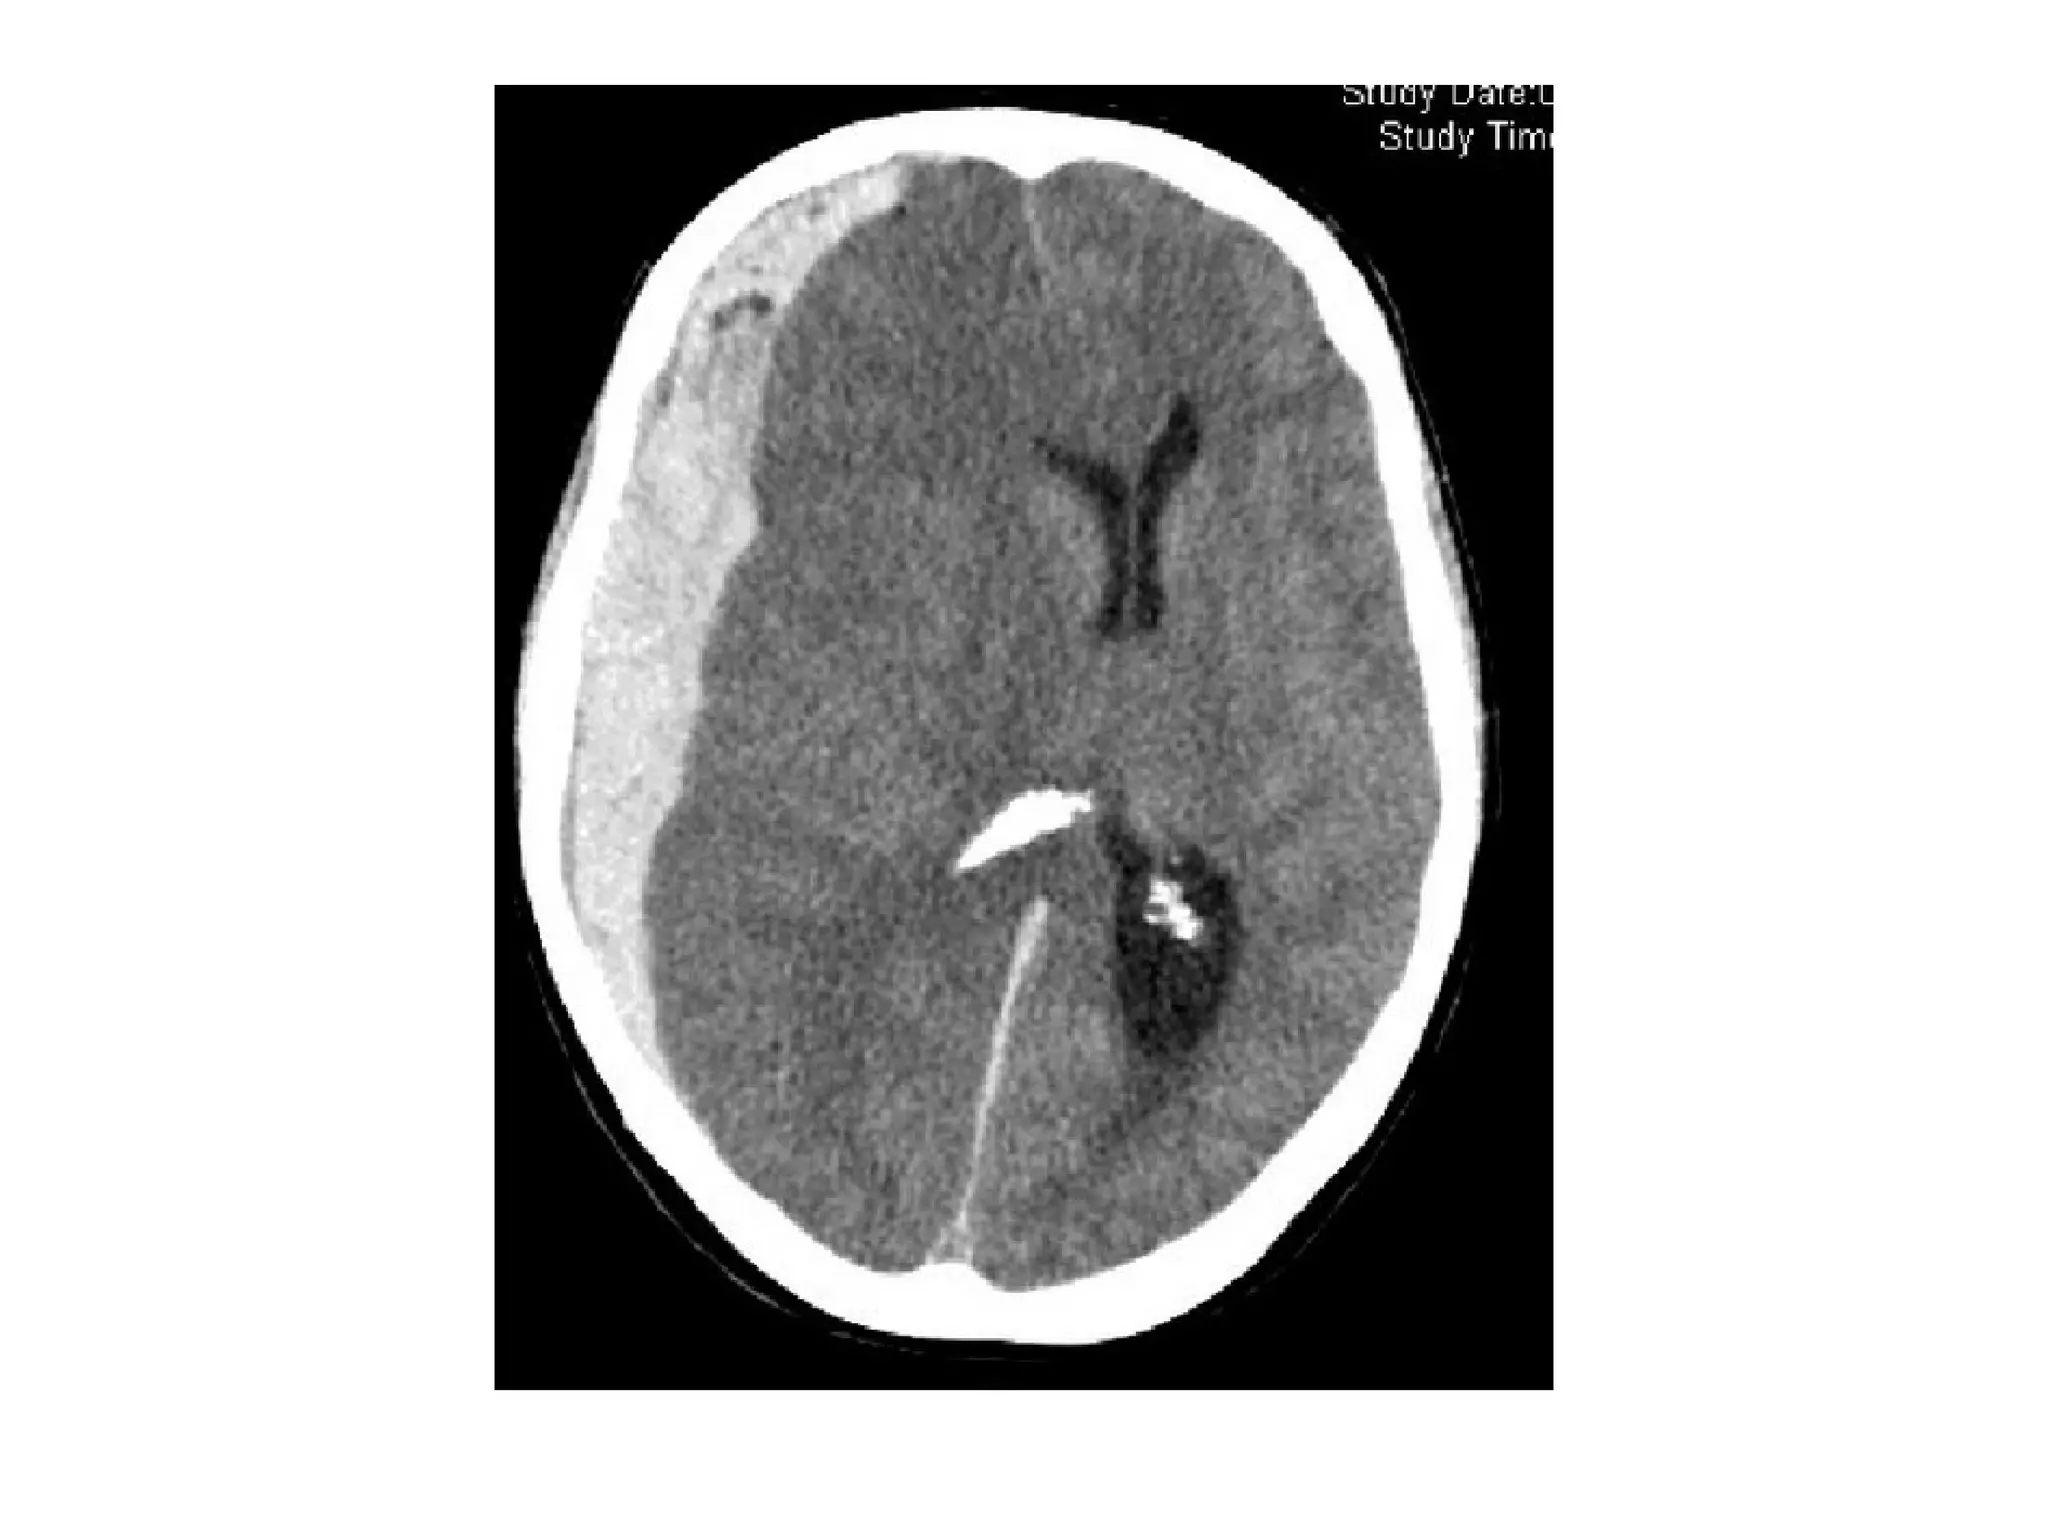

CT and T2W-gradient echo image of a hemorrhagic infarction

limited to the territory of the lateral lenticulostriate arteries